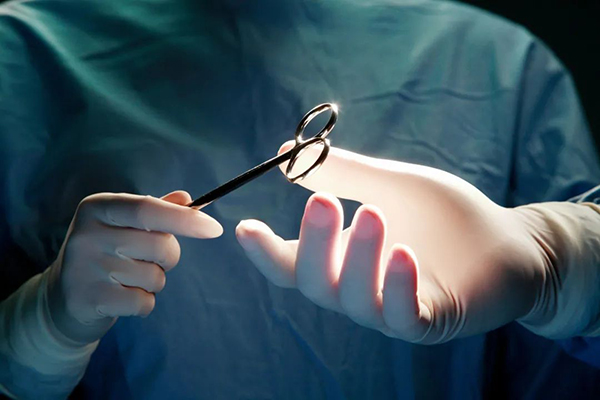

得了肝癌,该如何治疗?

如果能够做到早期发现的话,肝癌是能够根治的。直径小于3厘米的、单发肝癌病灶,是完全可以通过外科手术切除而治愈的,甚至都不用开膛破肚的去做外科开刀手术,只需要做腹腔镜微创手术,打上几个小孔,把一个很小的内窥镜放到腹腔里去,就能把小肝癌完整的切下来。

图库版权图片,不授权转载